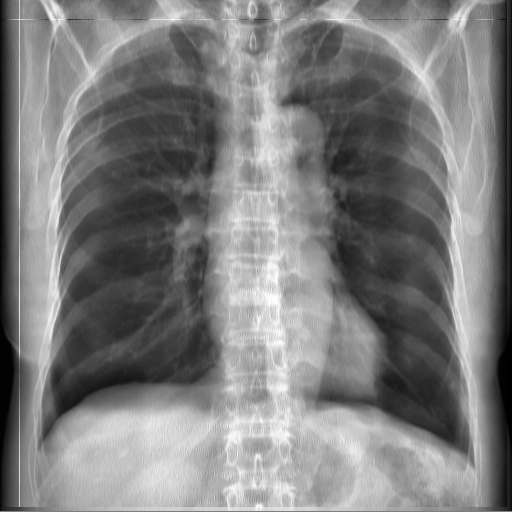

3.3 Applicability to Real X-ray

In order to explore the applicability of our algorithm to real X-ray and to examine whether the enhancement scheme introduces artifacts detrimental to CAD detection performance, we chose to perform the lung enhancement algorithm as a preprocessing step on nodule and mass CAD input images.

To accomplish this, we trained and tested a CheXNet [5] based network on 67,313 images released in ChestX-ray14 dataset(subset of PA images). In Figure 8 we show the results of the enhancement on an image from NIH ChestX-ray14 dataset [4]. The architecture we chose was a DenseNet-121 based network, with 512×512512512512\times 512 input size. Network weights were initialized with pretrained ImageNet weights and training was performed independently for enhanced images and non-enhanced images.

The dataset was split to 44,971 training, 11,245 validation and 11,097 test images. Results are given on the official test set in terms of average precision (AP) for the labels mass and nodule. We see a moderate increase in AP scores for the mass detection task (Table 2).

Refer to caption

(a)

(b)

(c)

(d)

Figure 8: Enhancement result on NIH ChestX-Ray14 image. One network was trained on the original X-ray and a second network was trained on the enhanced X-ray (a) Original X-ray (b) Enhanced X-ray (c) Zoom (d) Zoom -Enhanced